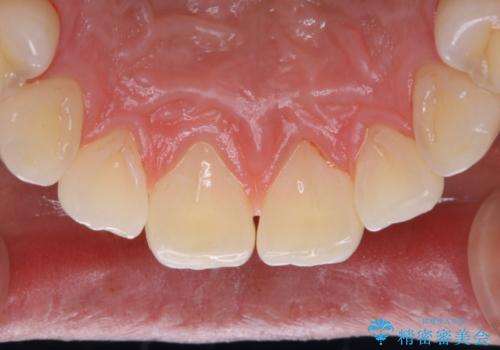

PMTCを行うことで、ご自身本来の歯の色になり自然な明るさになります。

また、ホワイトニングを考えている場合も、まずはPMTCで汚れの除去を行って判断することをおすすめします。